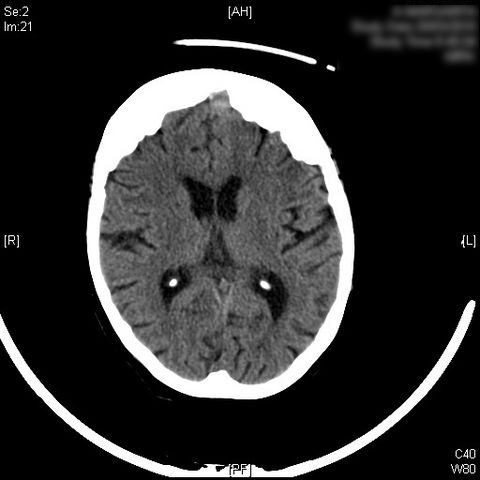

AVC amplio de territorio de A. cerebral media

Hematoma subdural por caída.

Atrofia cortico-subcortical de predominio frontotemporal.